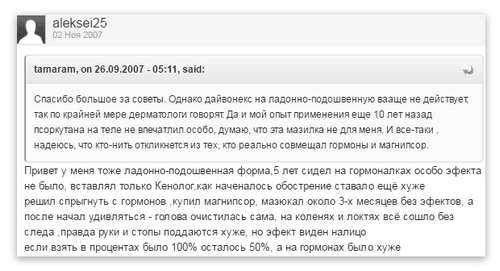

- В першу чергу треба зняти родобриденьнегормональні перевірені засоби: саліцилову мазь. дьоготь проти псоріазу (його можна змішувати з саліцилової маззю), солідоловая мазі. Відгуки про лікування долонно-підошовного псоріазу мазями:

Відгук про лікування долонно-підошовного псоріазу мазями